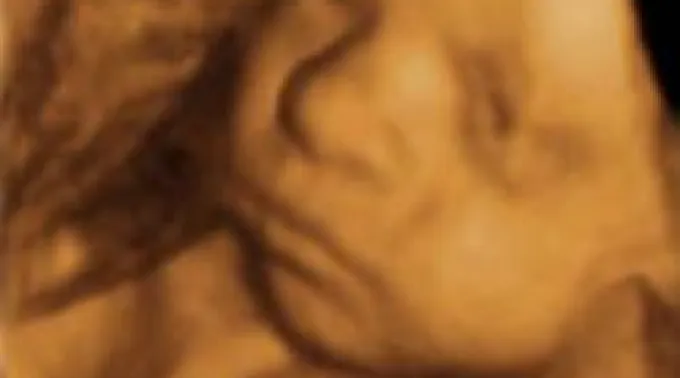

A lei assinala que um médico deve realizar um ultra-som 24 horas antes de um aborto, exceto em casos de emergência médica, e mostrar a imagem à mãe, fazendo que ela escute os batimentos do coração do coração do feto.

Entretanto, a mulher pode optar por não ver a imagem ou escutar os batimentos do coração. Para isso deverá assinar uma declaração antes que se faça o ultra-som.